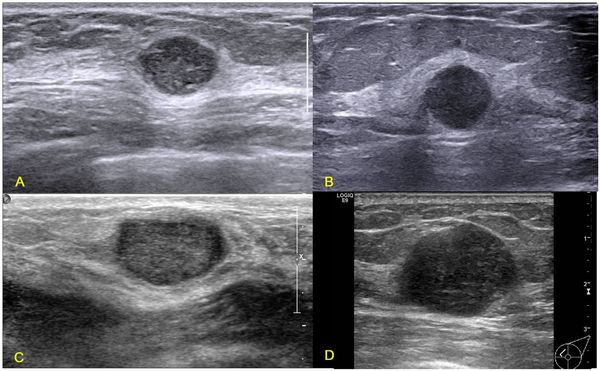

Феномен гипердиагностики в маммографии: примеры и иллюстрации

Раздел: Образы вокруг